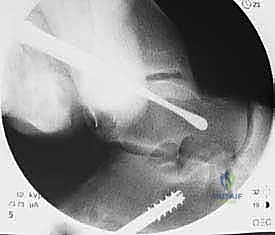

4. حفر الأنفاق العظمية:

باستخدام أدوات جراحية دقيقة، يقوم الدكتور هطيف بعمل أنفاق صغيرة جداً في عظم الشظية (Fibula) وعظم الكاحل (Talus) وعظم العقب (Calcaneus). تعتمد هذه الخطوة على المعرفة التشريحية العميقة لضمان وضع الأربطة الجديدة في مسارها التشريحي الطبيعي (Anatomical Reconstruction).

5. تثبيت الطعم:

يتم تمرير الطعم داخل الأنفاق العظمية وتثبيته بقوة باستخدام براغي تداخلية (Interference screws) مصنوعة من مواد تذوب حيوياً وتندمج مع العظم بمرور الوقت. يتم ضبط شد الطعم بدقة لضمان ثبات الكاحل مع الحفاظ على نطاق الحركة الطبيعي.